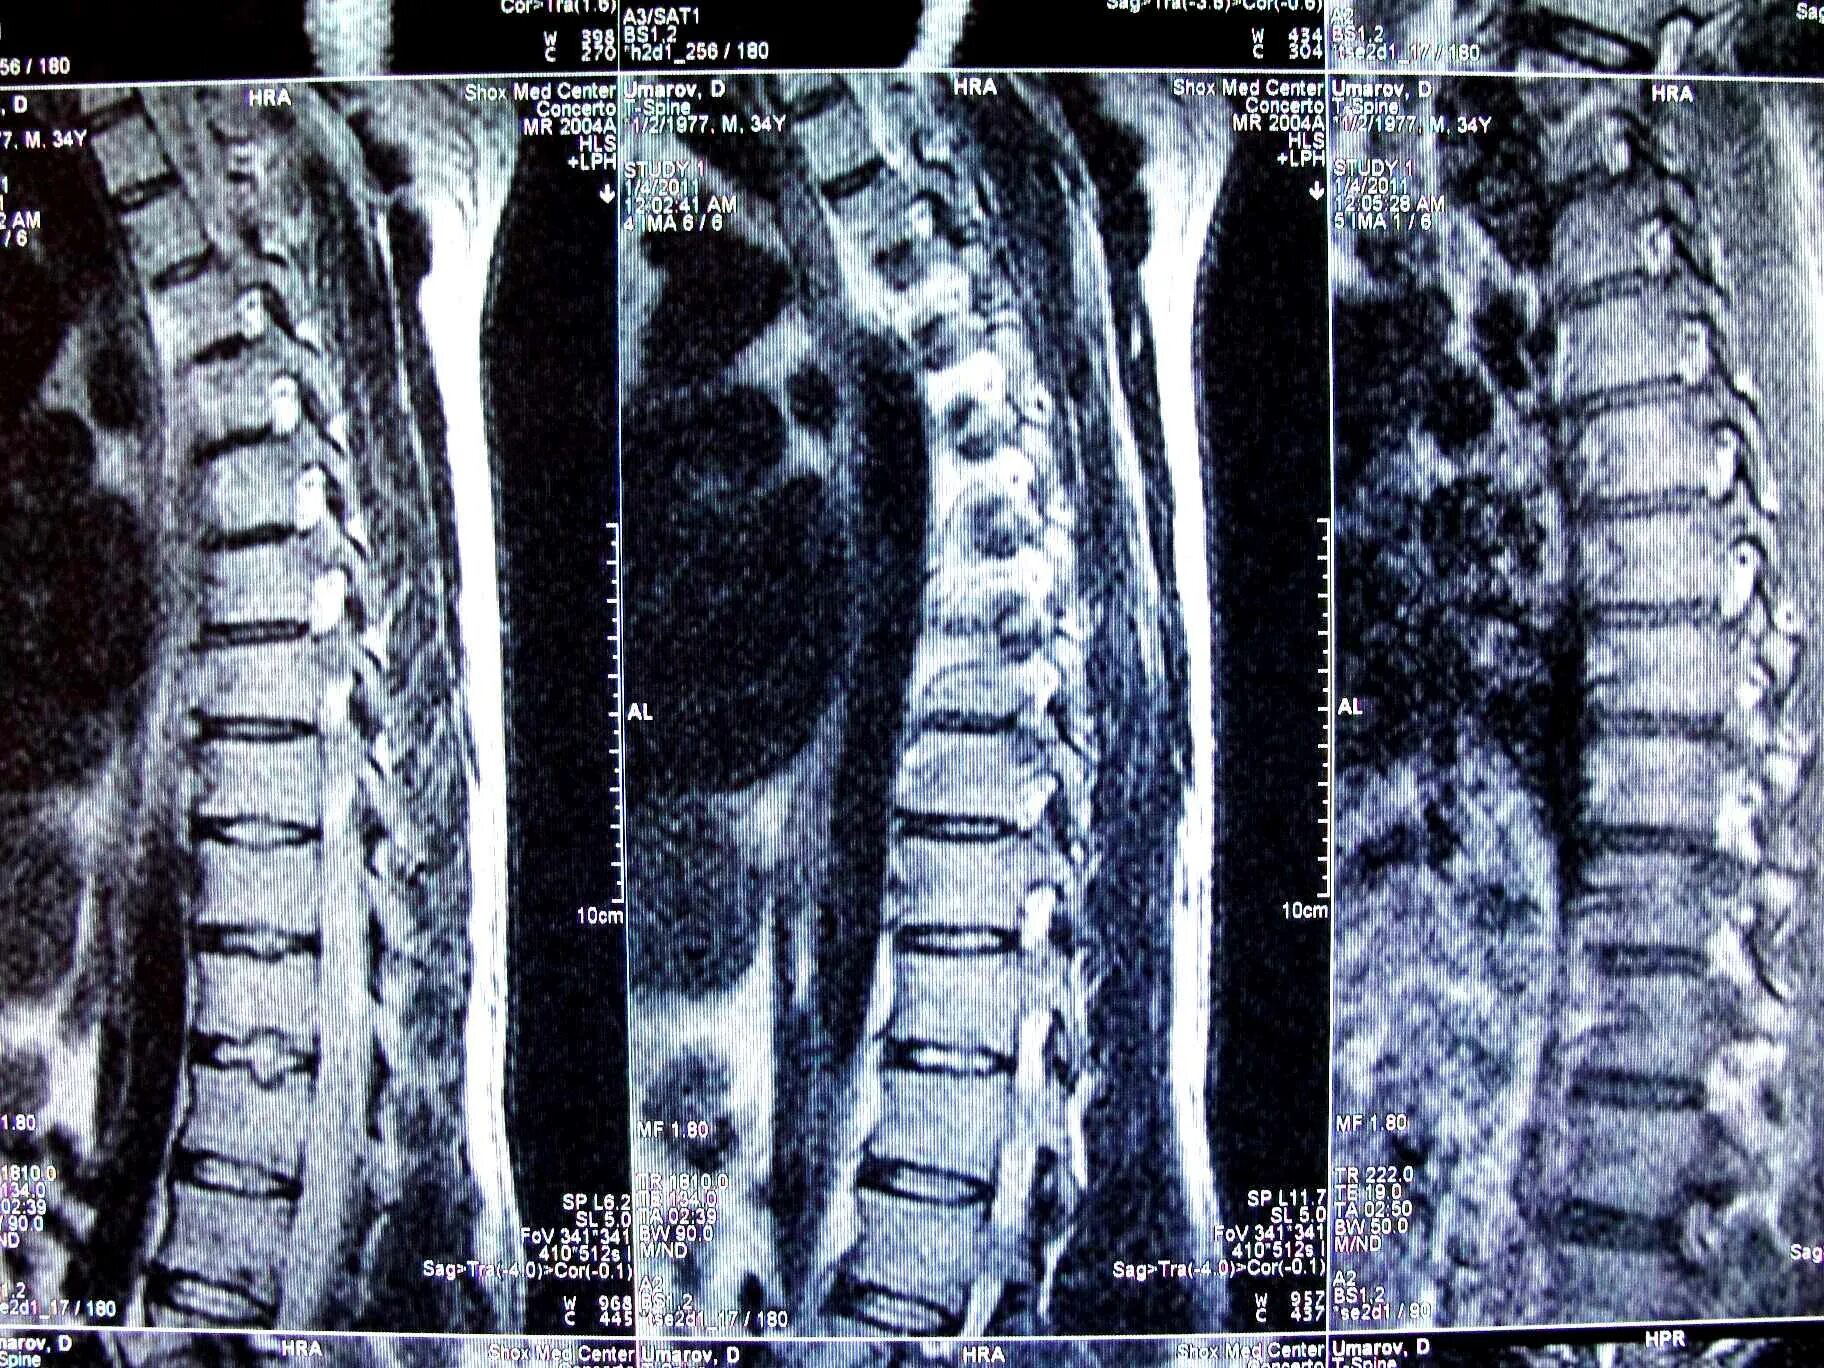

Протрузии шморля